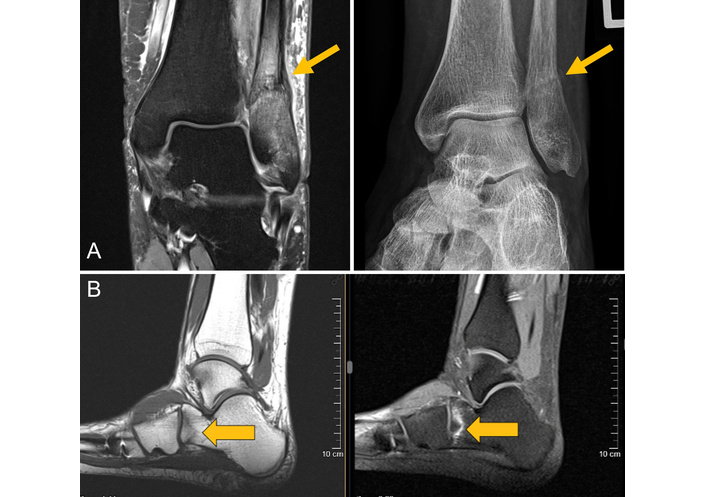

MRI of two and the corresponding radiograph of one patient. (A) Images of a 57-year-old female patient with an osteodestructive course of RA presenting with lateral right ankle pain for about 6 weeks. Both the radiograph and the coronal proton density–weighted turbo spin-echo fat-saturated MRI show a juxtasyndesmal IF of the fibula with reactive thickening of the periosteum and mineralization because of callus formation (gray arrows). (B) MRI of a 42-year-old female PsA patient treated with glucocorticoids and multiple csDMARDs, bDMARDs, and tsDMARDs for approximately 10 years. The T1w-MRI shows a blurred zigzag-shaped hypointense fracture line at the anterior calcaneus with surrounding BME depicted by the STIR MRI sequence. IF: insufficiency fracture; MRI: magnetic resonance imaging; BME: bone marrow edema; T1w: T1-weighted; STIR: short tau inversion recovery; csDMARD: conventional synthetic disease-modifying anti-rheumatic drugs; bDMARD: biologic disease-modifying anti-rheumatic drugs; tsDMARD: targeted synthetic disease-modifying anti-rheumatic drugs. Reprinted from [31]. © 2023 by the Journal of Rheumatology.